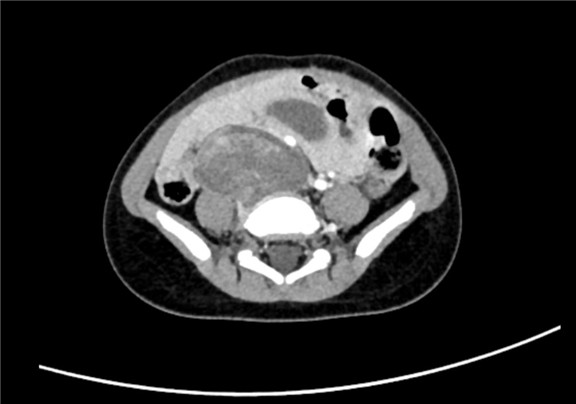

2017-7-4 腹部CT平扫 下腹部及盆腔占位性病变大小约5.4*4.2*4.5cm。

术前CT检查:

静脉期